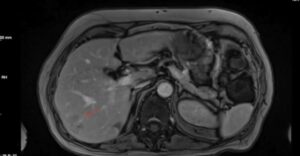

Ο εργαστηριακός έλεγχος ανέδειξε σημαντικά αυξημένα επίπεδα αγγειοδραστικού εντερικού πεπτιδίου (VIP), ενώ η απεικόνιση κατέδειξε όγκο στην ουρά του παγκρέατος με ηπατικές μεταστάσεις στα τμήματα VI, VII και III. Από το ατομικό αναμνηστικό αναφερόταν λαπαροσκοπική χολοκυστεκτομή.